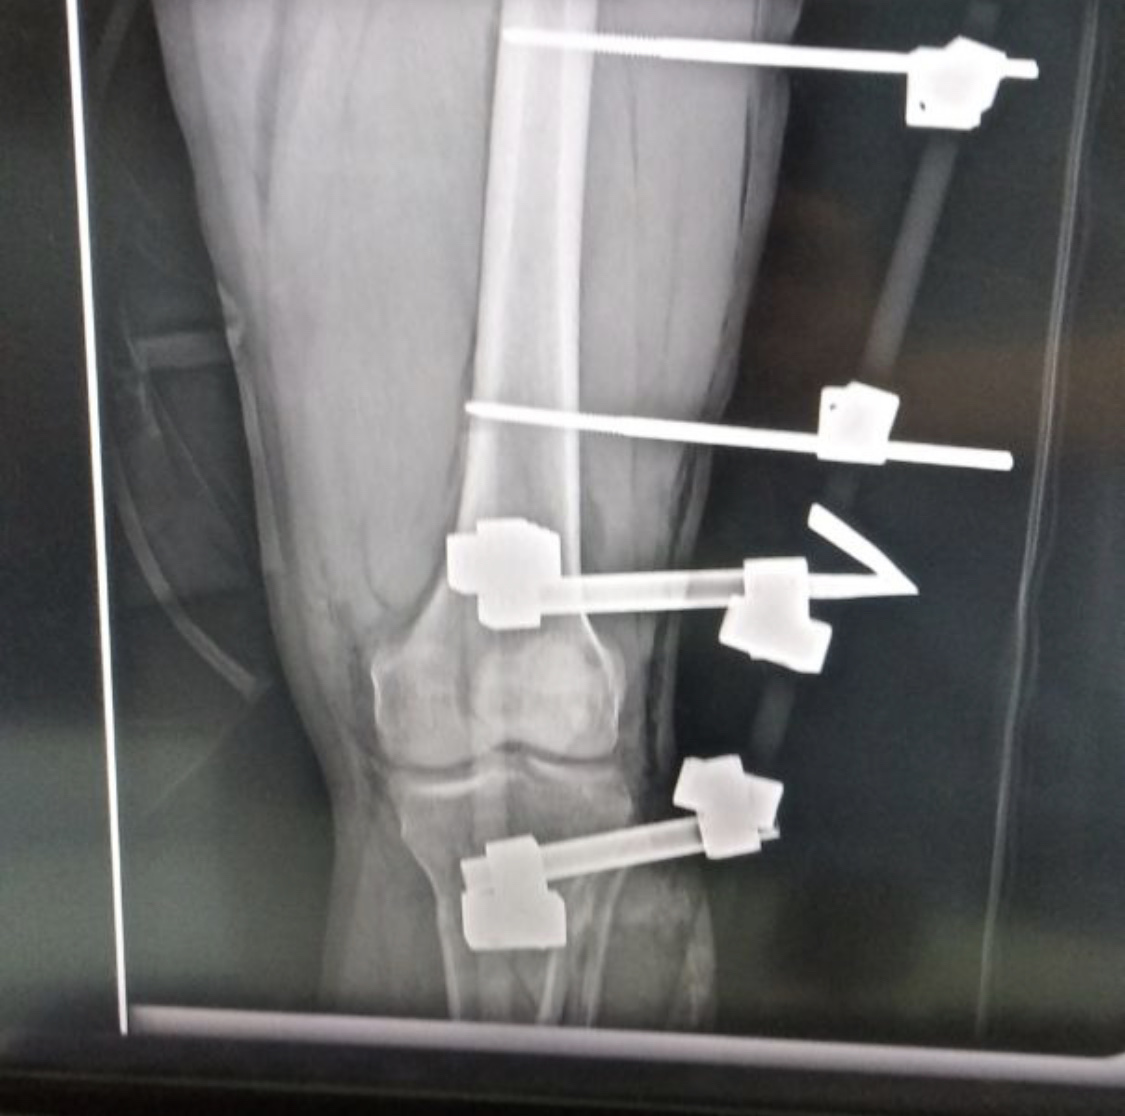

У бою під Роботиним захисник отримав важкі ураження обох ніг. До лікарні його доправили з уламковим пораненням, подвійним вогняним відкритим перелом лівої гомілки. Витягти вороже залізо з його правої ноги лікарям поки не вдалось.